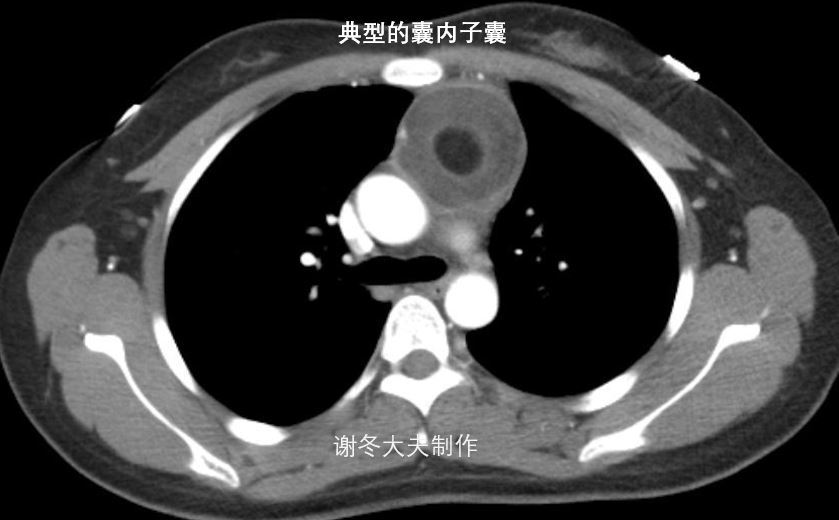

5.谢大夫,这个前纵隔占位,是胸腺瘤吗?

回答:这也是一个纵隔畸胎瘤,不是胸腺瘤,这个肿瘤内部有个非常典型的囊内子囊,这也是典型纵隔畸胎瘤的表现。